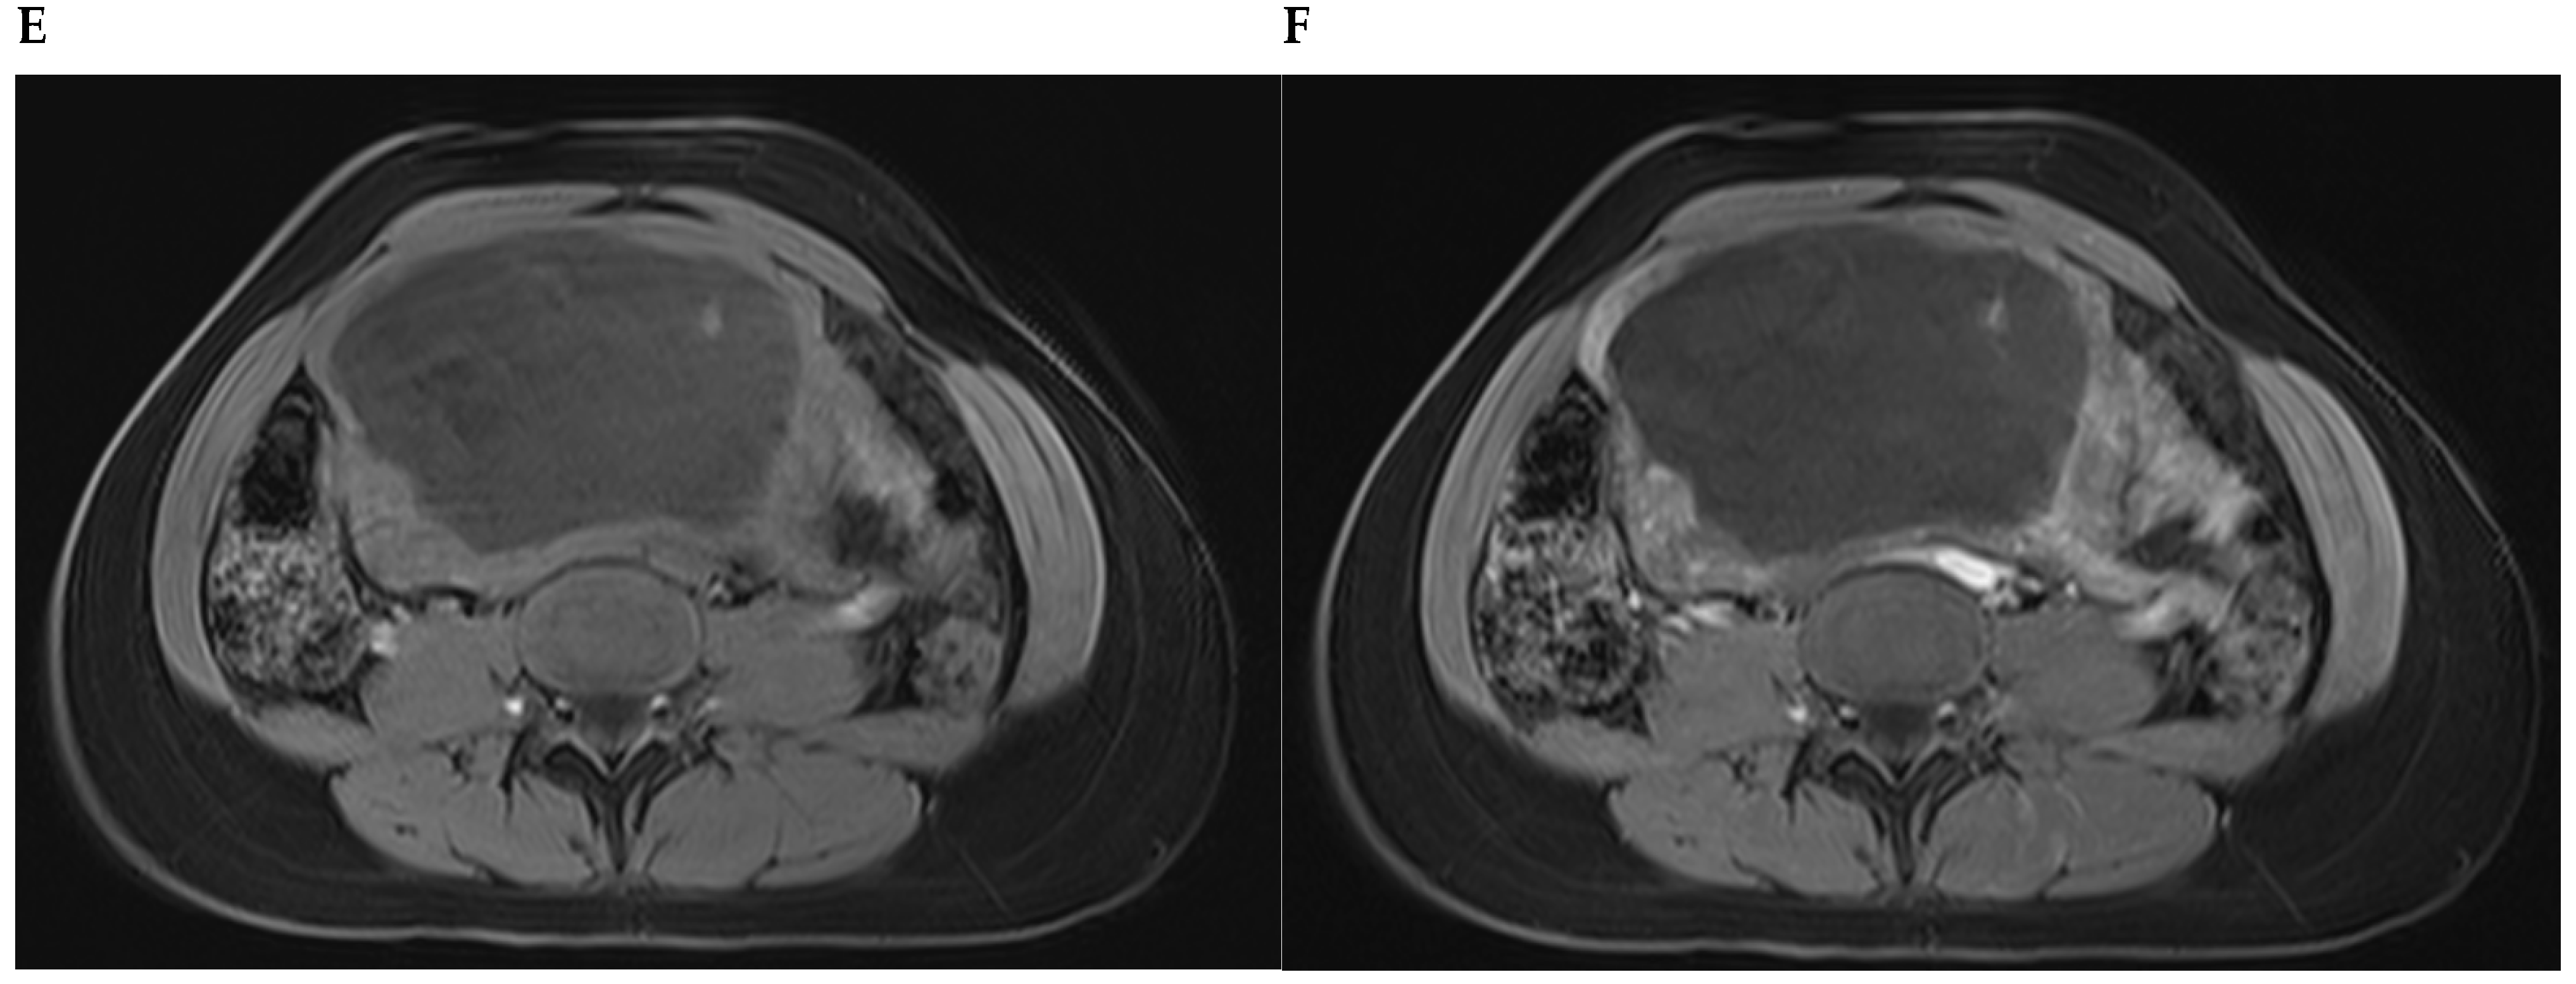

Figure 3. A woman with non-oral contraceptive user, presented to the outpatient clinic requesting a second opinion concerning a 240 mm sized uterine leiomyioma found by ultrasound at a different healthcare center. A computed tomography showed a uterine multinodular lesion with signs of degeneration. The patient received magnetic resonance imaging examination (Figure 3) and surgery with total myomectomy and specimen histopathological analyses (Figure 4). Herein, Figure 3 shows a subserosal-pedunculated leiomyoma with hyaline and cystic degeneration in a 29-year-old woman. (A) Axial and (B) coronal T2-weighted (T2) Dixon magnetic resonance imaging (MRI) showed a normal-sized uterus with axial organ rotation by 180° in an anticlockwise direction. From the right cornual region of the uterus, there was a low signal intensity (T2) subserosal-pedunculated mass (FIGO 7). This well-circumscribed, giant abdominopelvic mass measured approximately 173 × 84 × 174 mm and presented signs of cystic degeneration on its most cranial portion by demonstrating an internal, round, well-defined area with homogeneous fluid-like high signal intensity (T2), best represented on (C) axial and (D) coronal T2 half-Fourier acquisition single-shot turbo spin-echo MRI. It also demonstrated (E) low-signal intensity on non-contrast axial T1-weighted (T1) Dixon MRI, (F) without enhancement on arterial axial T1 Dixon MRI, further suggesting cystic degeneration (up to 80% of histological distribution of degeneration area) of this giant leiomyoma.